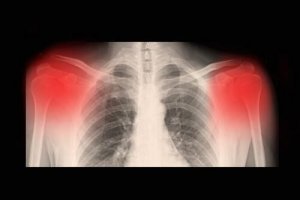

Діагностувати це захворювання можна за допомогою медичного обстеження. Зазвичай для цього використовують рентген, комп’ютерну томографію та магнітно-резонансну терапію. Вид остеоартриту можна визначити за допомогою ультразвуку високої роздільної здатності.